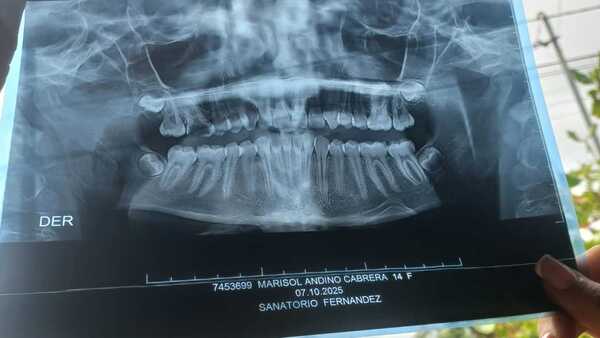

En vez de fiesta de 15 pidió poder operarse

La cirugía cuesta más de G. 15 millones. Ya no puede ni comer por un problema en la mandíbula. ...[Leer más]